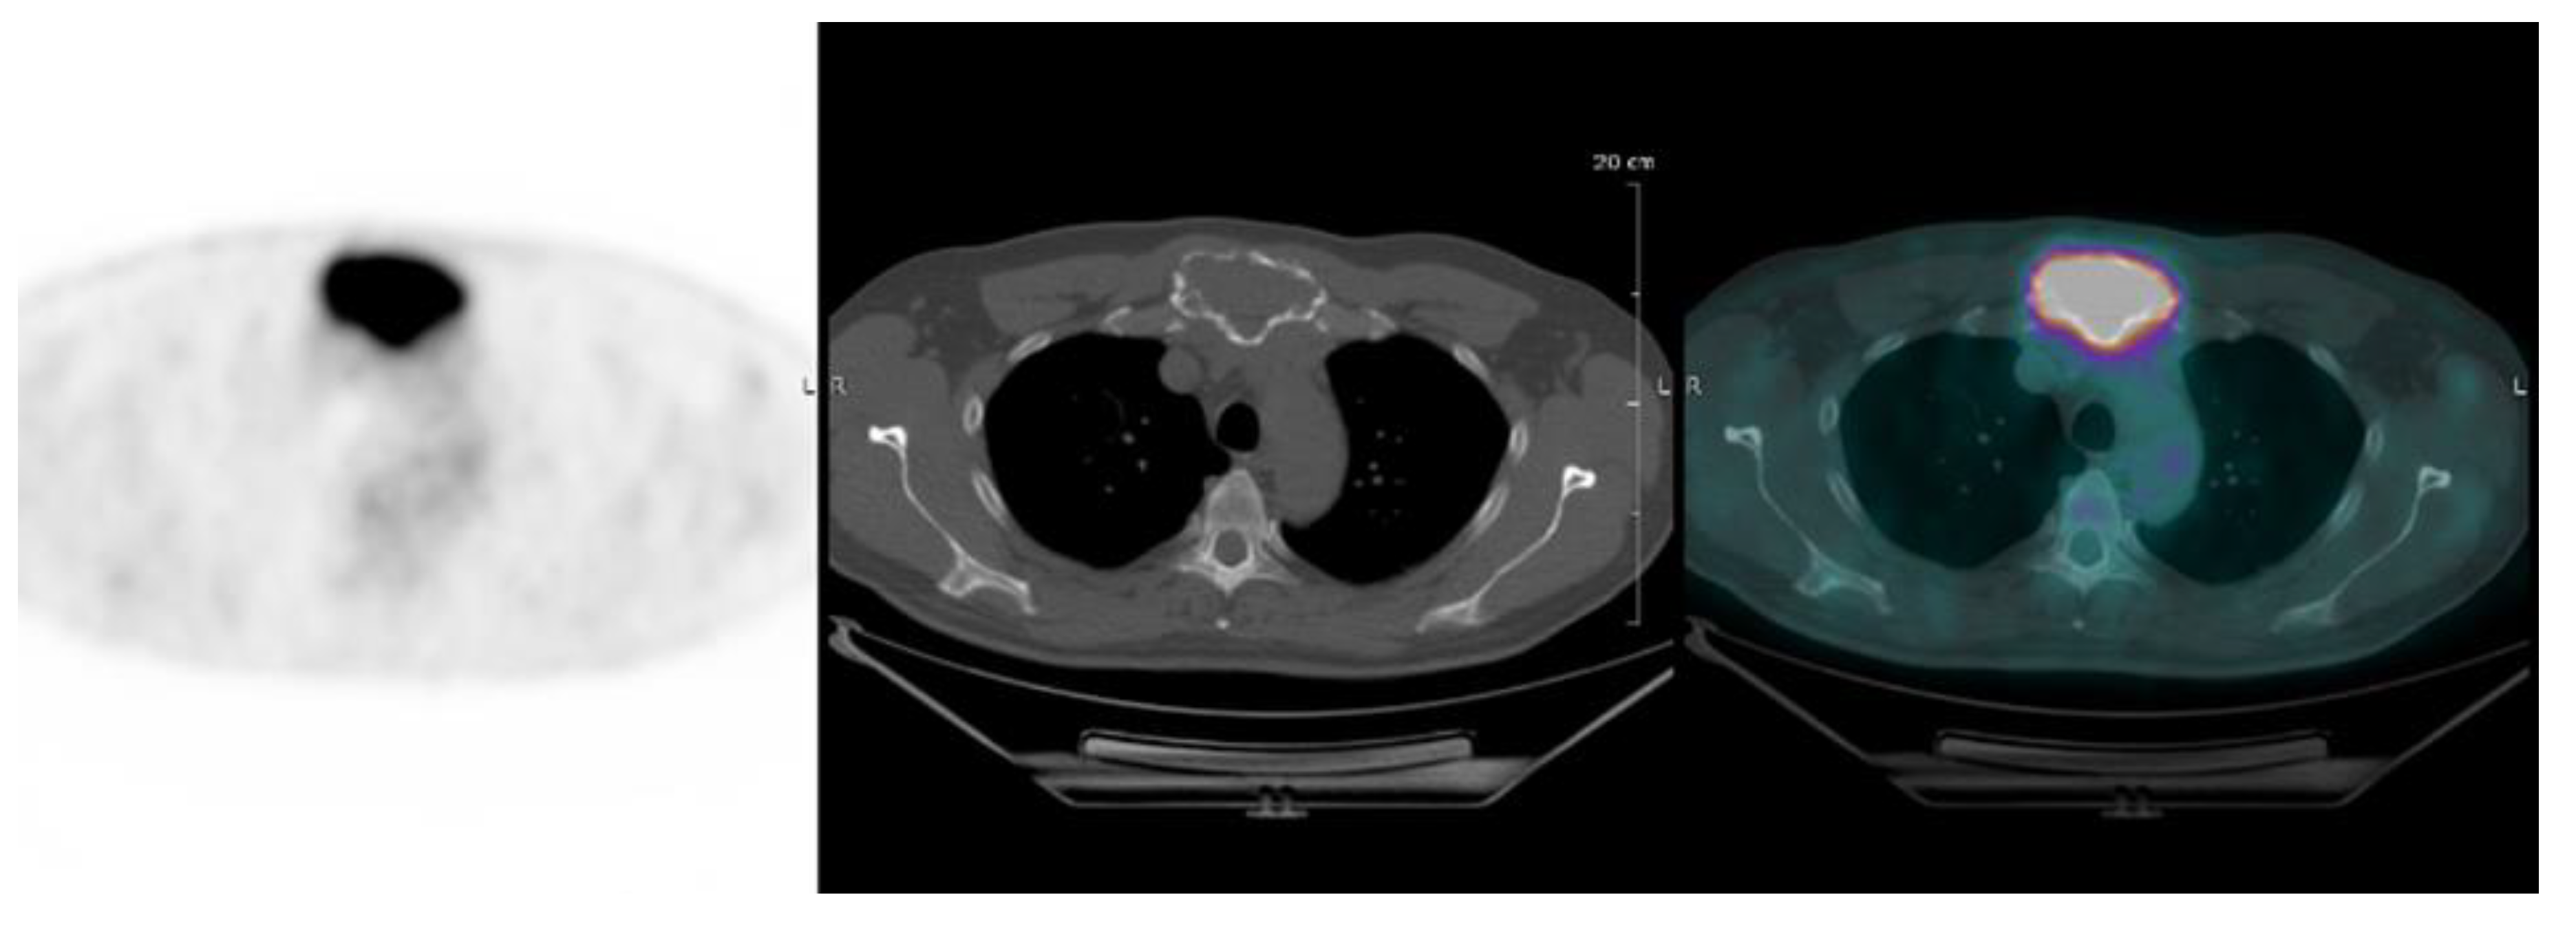

| Focal lesion | Foci of uptake above the surrounding background noise on two successive sections with or without osteolysis on the CT image | Suggested as pejorative prognostic biomarker using cut off 3. | Bartel et al., 2009 [8] |

| EMD | Tissue invasion without contiguous bone involvement. | Presence of EMD suggested as pejorative prognostic biomarker | Zamagni et al., 2011 [9] |

| PMD | Soft tissue invasion with contiguous bone involvement. | Presence of PMD suggested as pejorative prognostic biomarker | Moreau et al., 2019 [19] |

| FL SUVmax | Maximal SUVmax of bone focal lesions | Suggested as pejorative prognostic biomarker using cut off of 4.2 | Zamagni et al., 2011 [9] |

| FDG-PET/CT abnormality | Presence of Focal lesion(s) and/or EMD lesion(s) and/or PMD lesion(s) and/or diffuse medullary involvement. | Absence of FDG-PET/CT abnormality considered as a favourable prognostic | Rasche et al., 2017 [16] |